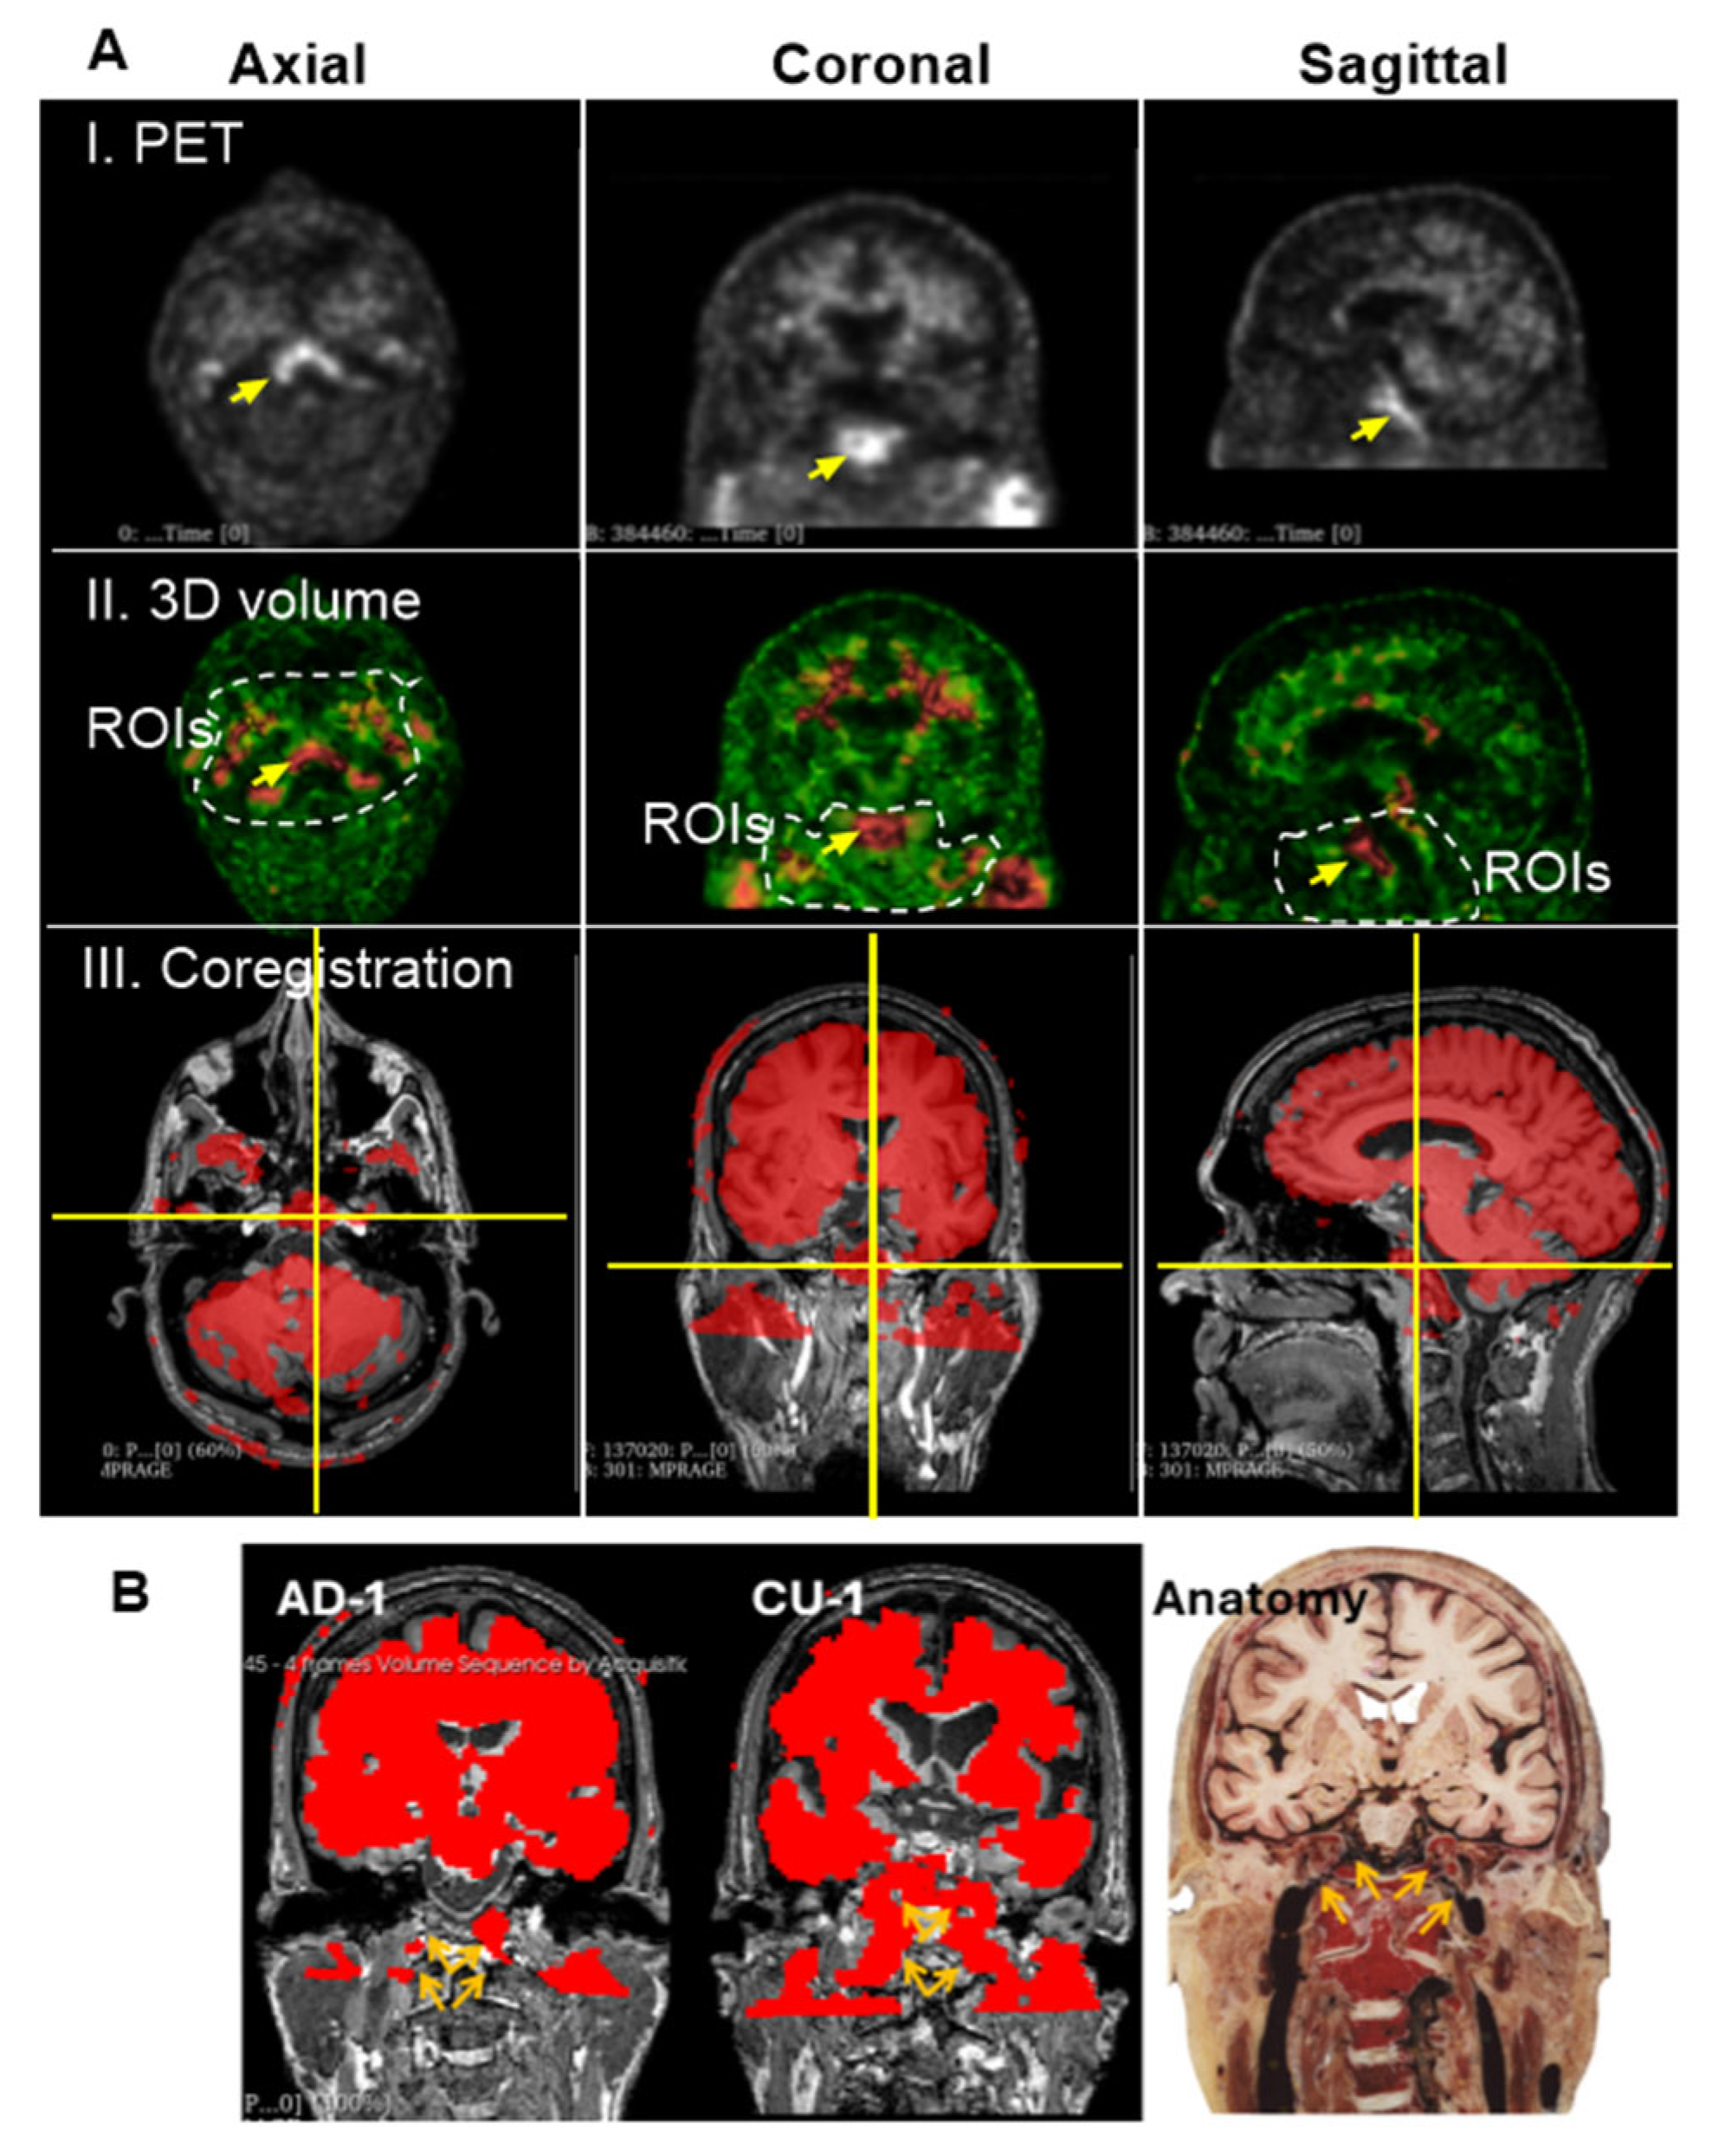

3.4. Group 3: Deep Cervical Areas

Unlike the skull, Aβ signal intensity in the deep cervical region is heterogeneous (Figure 2A), showing low in some ROIs and high in others. While low-intensity signals in this area also form canal-like networks, they appear more densely clustered than those observed in skull regions. High-intensity Aβ signals were localized to specific anatomical sites, as marked in Figure 6A(I,II). We hypothesized that these elevated signals in the deep cervical region may correspond to anatomical intersections involved in Aβ clearance pathways from the brain to peripheral lymphatic structures. To investigate this, we co-registered PET images with MRI scans from the same individuals to provide anatomical context for the high-intensity signals. This co-registration revealed that prominent Aβ signals were localized to the clivus of the occipital bone at the skull base (Figure 6A(III)). Additionally, high-intensity signals were observed along the internal carotid plexus (Figure 6B), suggesting that Aβ signals may extend beyond the cranial vault into structurally connected extracranial regions.

Figure 6. Group 3: the Deep Cervical Region. (A), High intensity of Aβ signals associated with the clivus bones. Prominent ROI, marked by yellow arrows, was consistently detected across PET scans of most individuals. Images displayed here are representatives of AD-1 (002_S_5018). Single arrow points to a region of high Aβ signal intensity located in the deep cervical area. (I), PET scan of a single slice at axial, coronal and sagittal planes. (II), 3D volume after reconstructing 3 individual slices for thickness. Dashed lines indicate the deep cervical areas. Aβ signal intensities range from green (low) to red (high). (III), Co-registration of PET/MRI reveals that this signal is anatomically aligned with the clivus, a bony structure at the base of the skull, anterior to the brainstem. The clivus is visualized at the intersection of the vertical and horizontal yellow lines across all three imaging planes. (B), PET signals are shown in red, representing Aβ tracer uptake. Images displayed here are representatives of CU-1 (002_S_0259) and AD-1 (002_S_5018). Brown arrays indicate the internal carotid plexus where Aβ signals in the place coregistered with MRIs of CU-1 and AD-1, respectively. The signals were associated with the internal carotid vessels entering the brain cavity. The anatomical illustration was excerpted from the Atlas of the Human Brain [15], and is used here to provide anatomical context for the described structure.